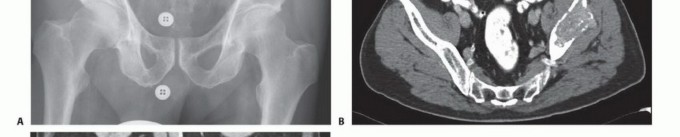

- الأشعة السينية (X-rays): هي الفحص الأولي، ويمكن أن تكشف عن التغيرات العظمية مثل التآكل أو التصلب أو الكسور.

- التصوير المقطعي المحوسب (CT Scan): يوفر صورًا مقطعية مفصلة للعظام والأنسجة الرخوة، ويساعد في تحديد حجم الورم، مدى انتشاره داخل العظم، وعلاقته بالهياكل المحيطة.

- المسح الذري للعظام (Bone Scintigraphy / Bone Scan): يكشف عن مناطق النشاط الأيضي المتزايد في العظام، مما يشير إلى وجود آفات سرطانية في مراحل مبكرة قد لا تظهر في الأشعة السينية.